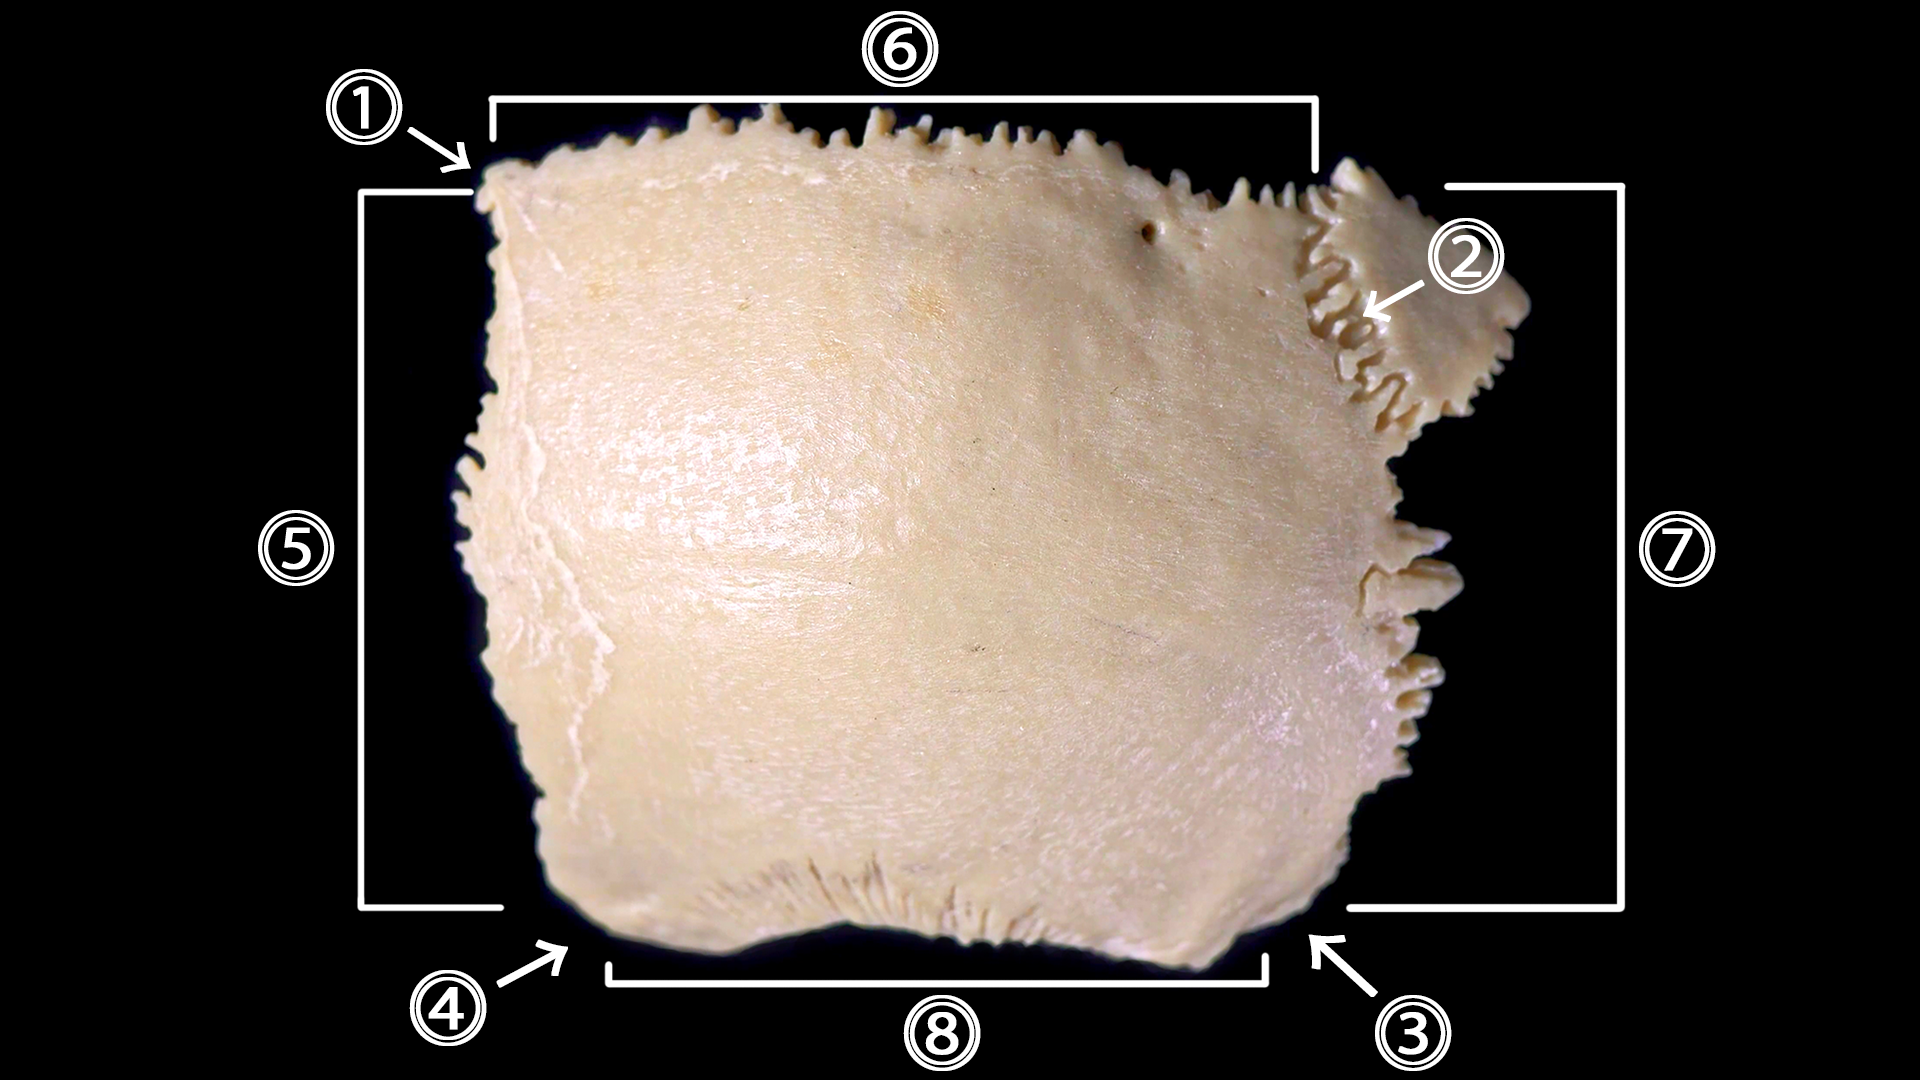

Кость четырехугольной формы, поэтому в ней выделяют 4 края и 4 угла.

Углы теменной кости:

• лобный угол (angulus frontalis) (1)

• затылочный угол (angulus occipitalis) (2)

• сосцевидный угол (angulus mastoideus) (3)

• клиновидный угол (angulus sphenoidalis) (4)

Края теменной кости:

• лобный край (margo frontalis) – (5)

• сагиттальный край (margo sagittalis) – (6)

• затылочный край (margo occipitalis) – (7)

• чешуйчатый край (margo squamosus) – (8)